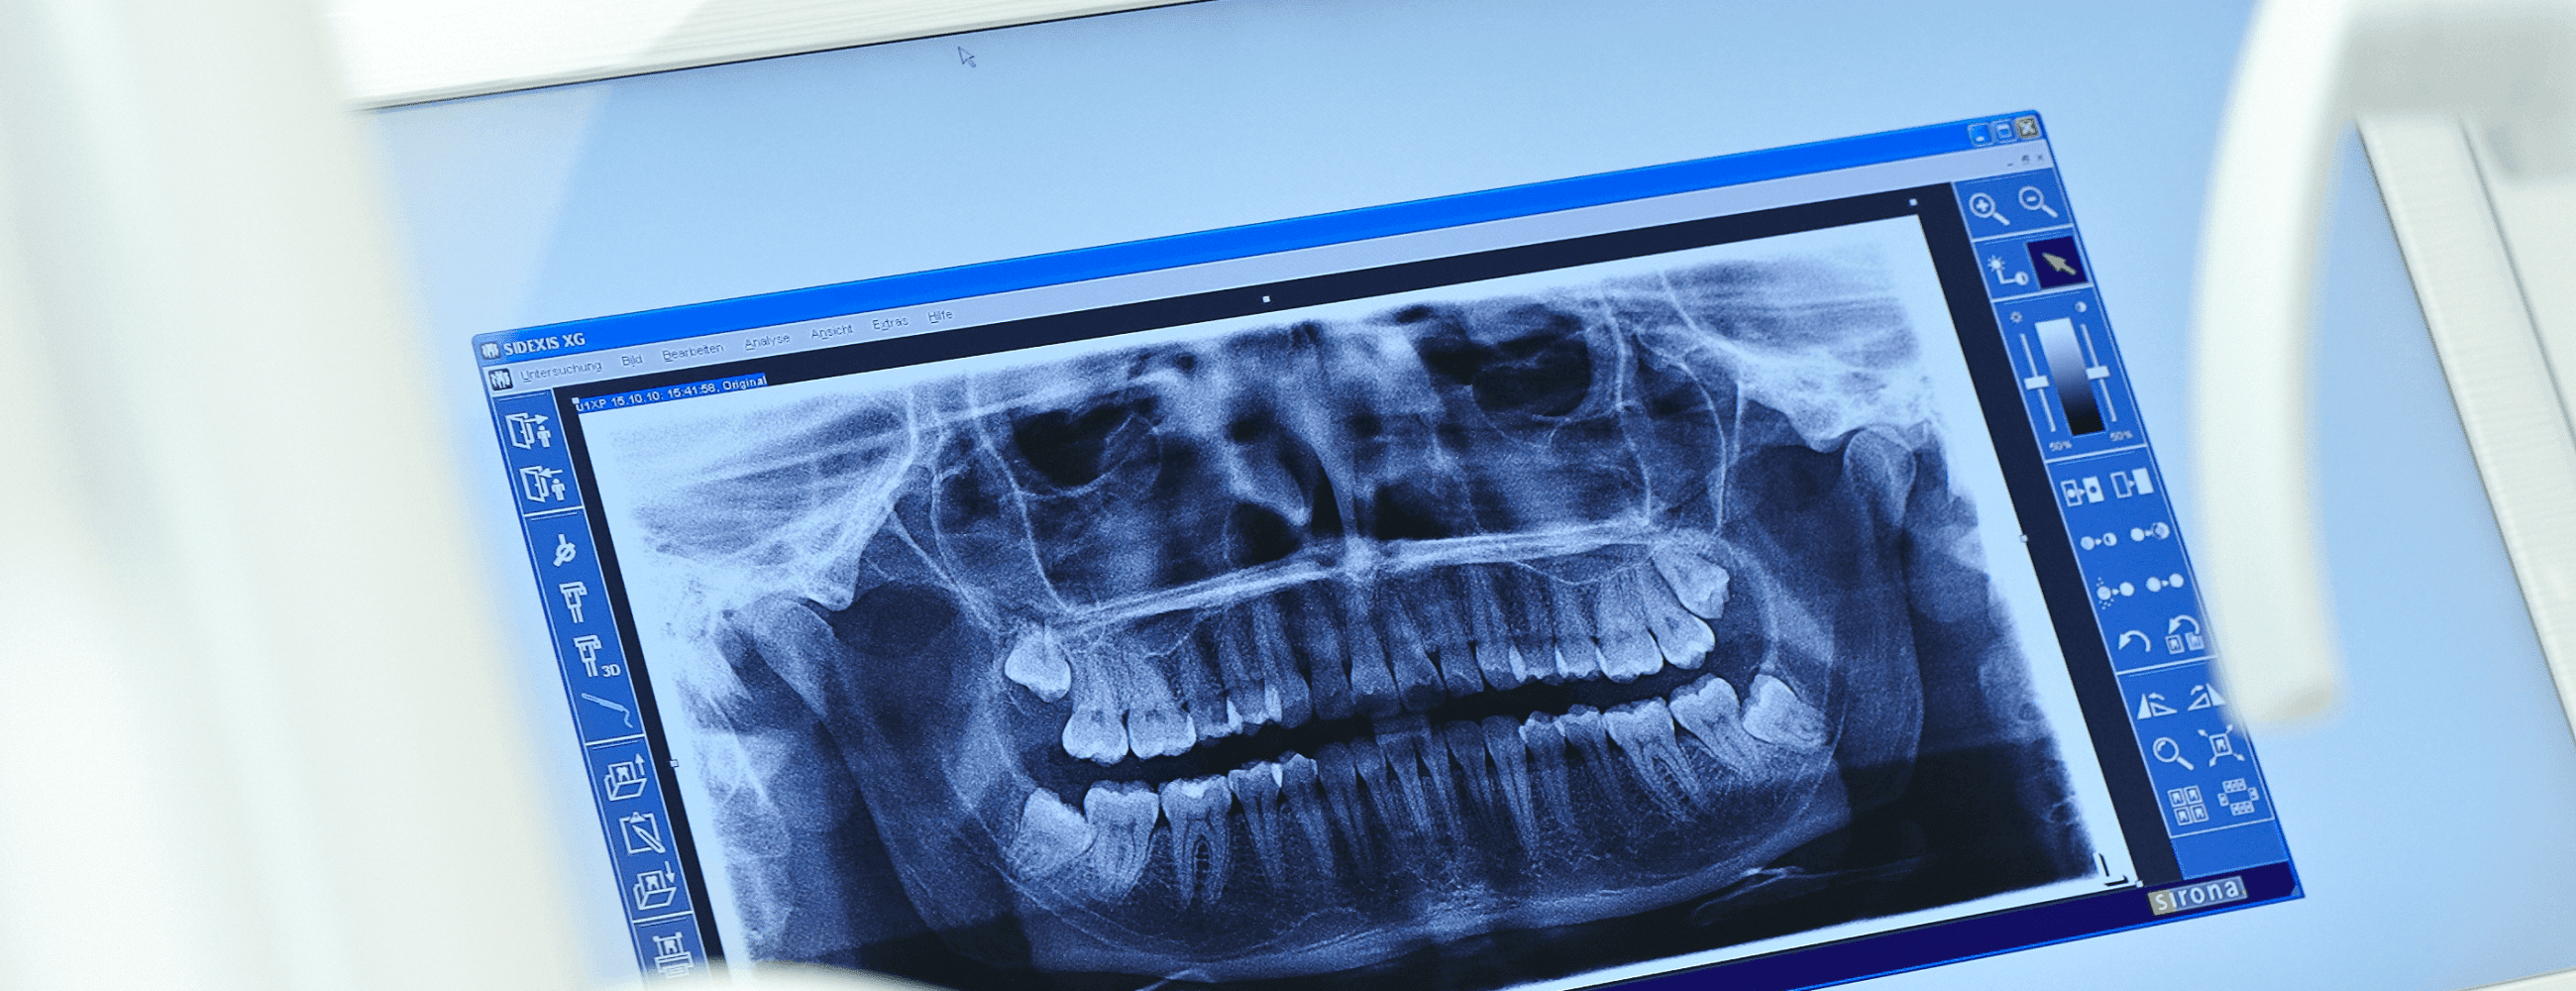

In Düsseldorf sind wir in unserer Zahnarzt-Praxis auf Wurzelbehandlungen spezialisiert. Die so genannte Endodontie gehört zu unseren Tätigkeitsschwerpunkten.

Für die Endodontie muss das feingliedrige Wurzelkanalsystem des Zahns gereinigt, keimfrei gemacht und gefüllt werden, damit die Stabilität der Wurzel und letztlich des Zahns erhalten bleibt. Gearbeitet wird bei uns in Düsseldorf Oberbilk mit allem, was optimale Therapieerfolge unterstützt. Die Lupenbrille sorgt für den Durchblick sowie digitale Längenmessung und die maschinelle Aufbereitung der Wurzelkanäle macht alle Regionen des Zahnwurzelsystems erreichbar. Die abschließende sogenannte thermoplastische Wurzelfüllung ermöglicht, dass das Füllungsmaterial in das Wurzelsystem hinein fließt und sich dabei den anatomischen Besonderheiten der Zahnwurzel anpasst.